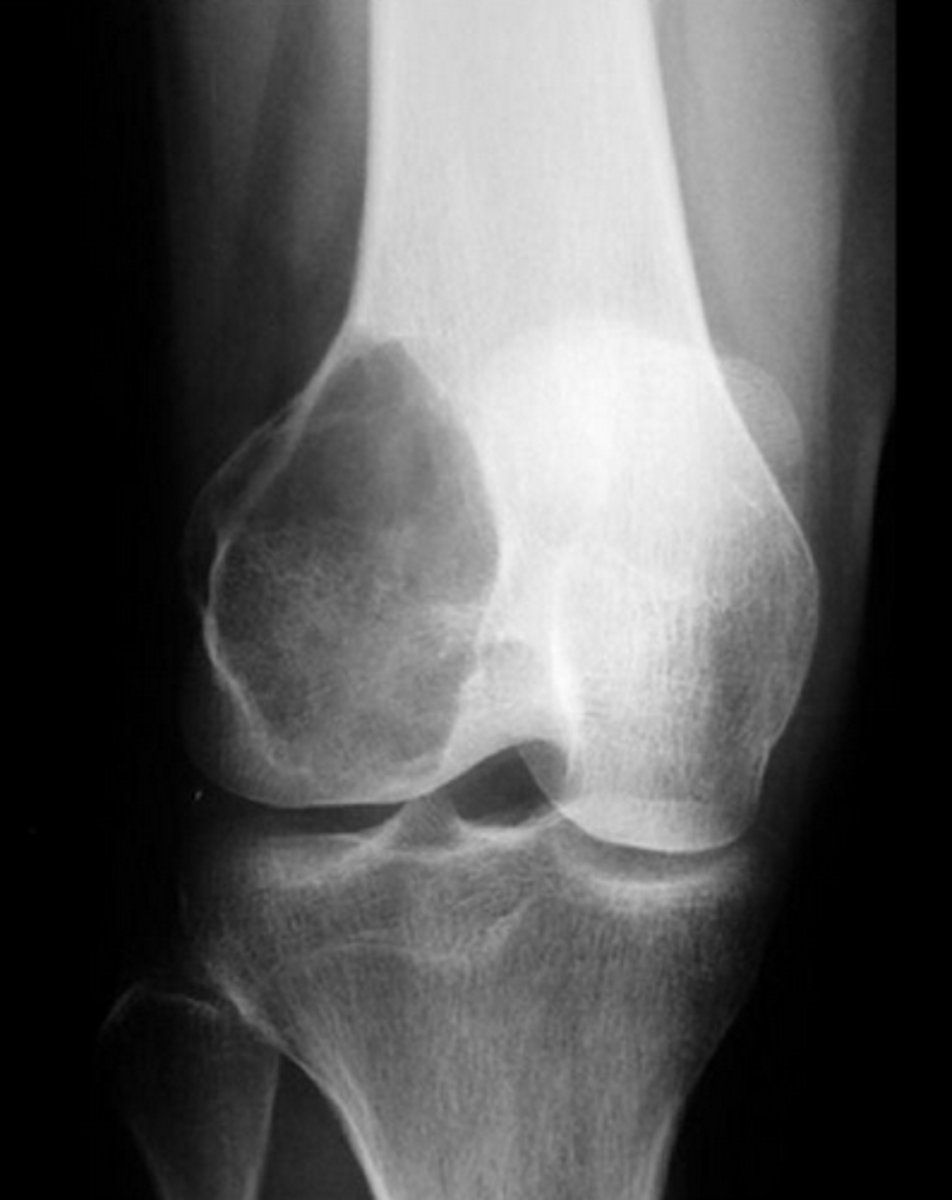

___ shows x-ray expansile and eccentric lytic area, pain, swelling in epiphysis of femur.

Giant cell tumor of bone

"soap bubble"

- benign, locally aggressive